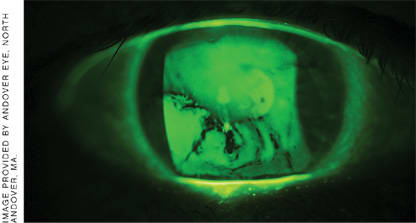

Figure. Tear film break-up in a dry eye patient. Break-up time drops below the 5 second threshold in over 90% of patients post-LASIK.

In dry eye, a tear film containing unhealthy or insufficient lipids, aqueous or mucins can become unstable, forcing it to frequently disperse before the eye has a chance to replenish it with a blink. This rapid tear film breakup time (TFBUT) results in inadequate ocular surface protection as measured by the ocular protection index (OPI).3

In a study investigating the effects of LASIK on dry eye, preoperative mean TFBUT was determined to be 5.32 seconds, a value not associated with dry eye. A day after surgery, this value had dropped to 4.14 seconds (suggesting a state of dry eye) and remained at a low 4.49 seconds a week after the procedure. Not until a month after LASIK did mean breakup time return to a level that was considered healthy (5.09 seconds).8